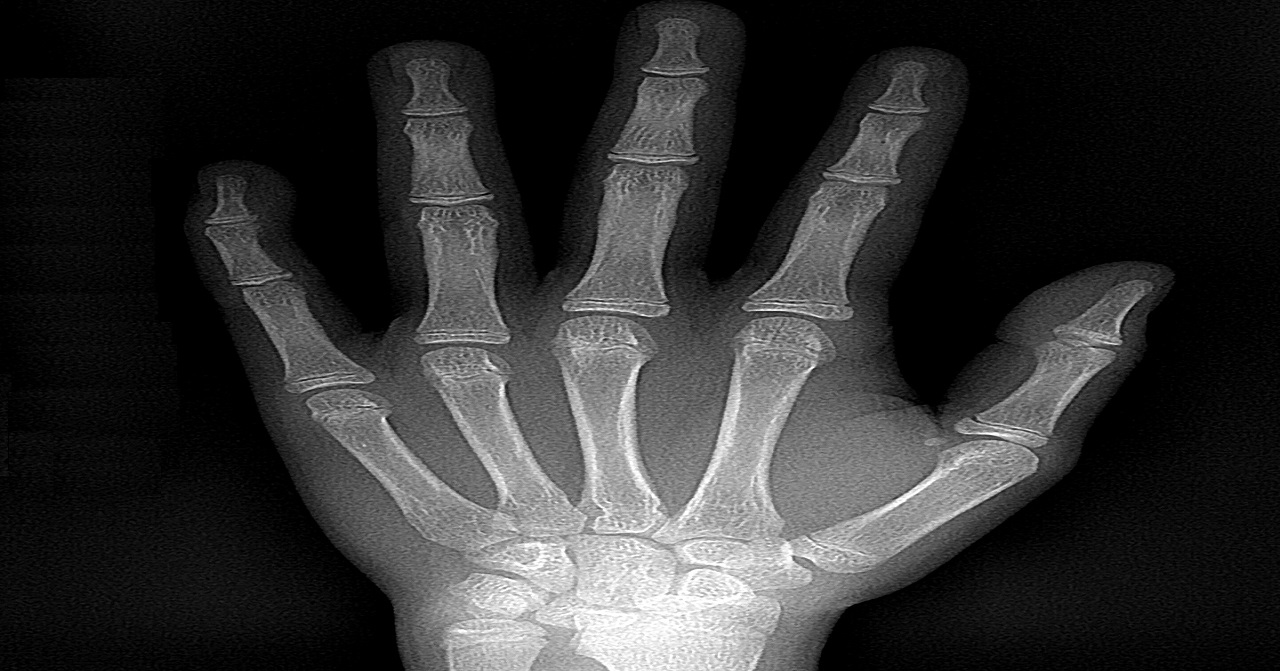

Carpal

El estudio radiográfico combinado de ATM está indicado para la valoración de disfunciones temporomandibulares así como fracturas condilares y subcondilares; este estudio comprende de dos radiografías de exposición lateral y posteroanterior de la articulación temporomandibular en posición abierta y cerrada.